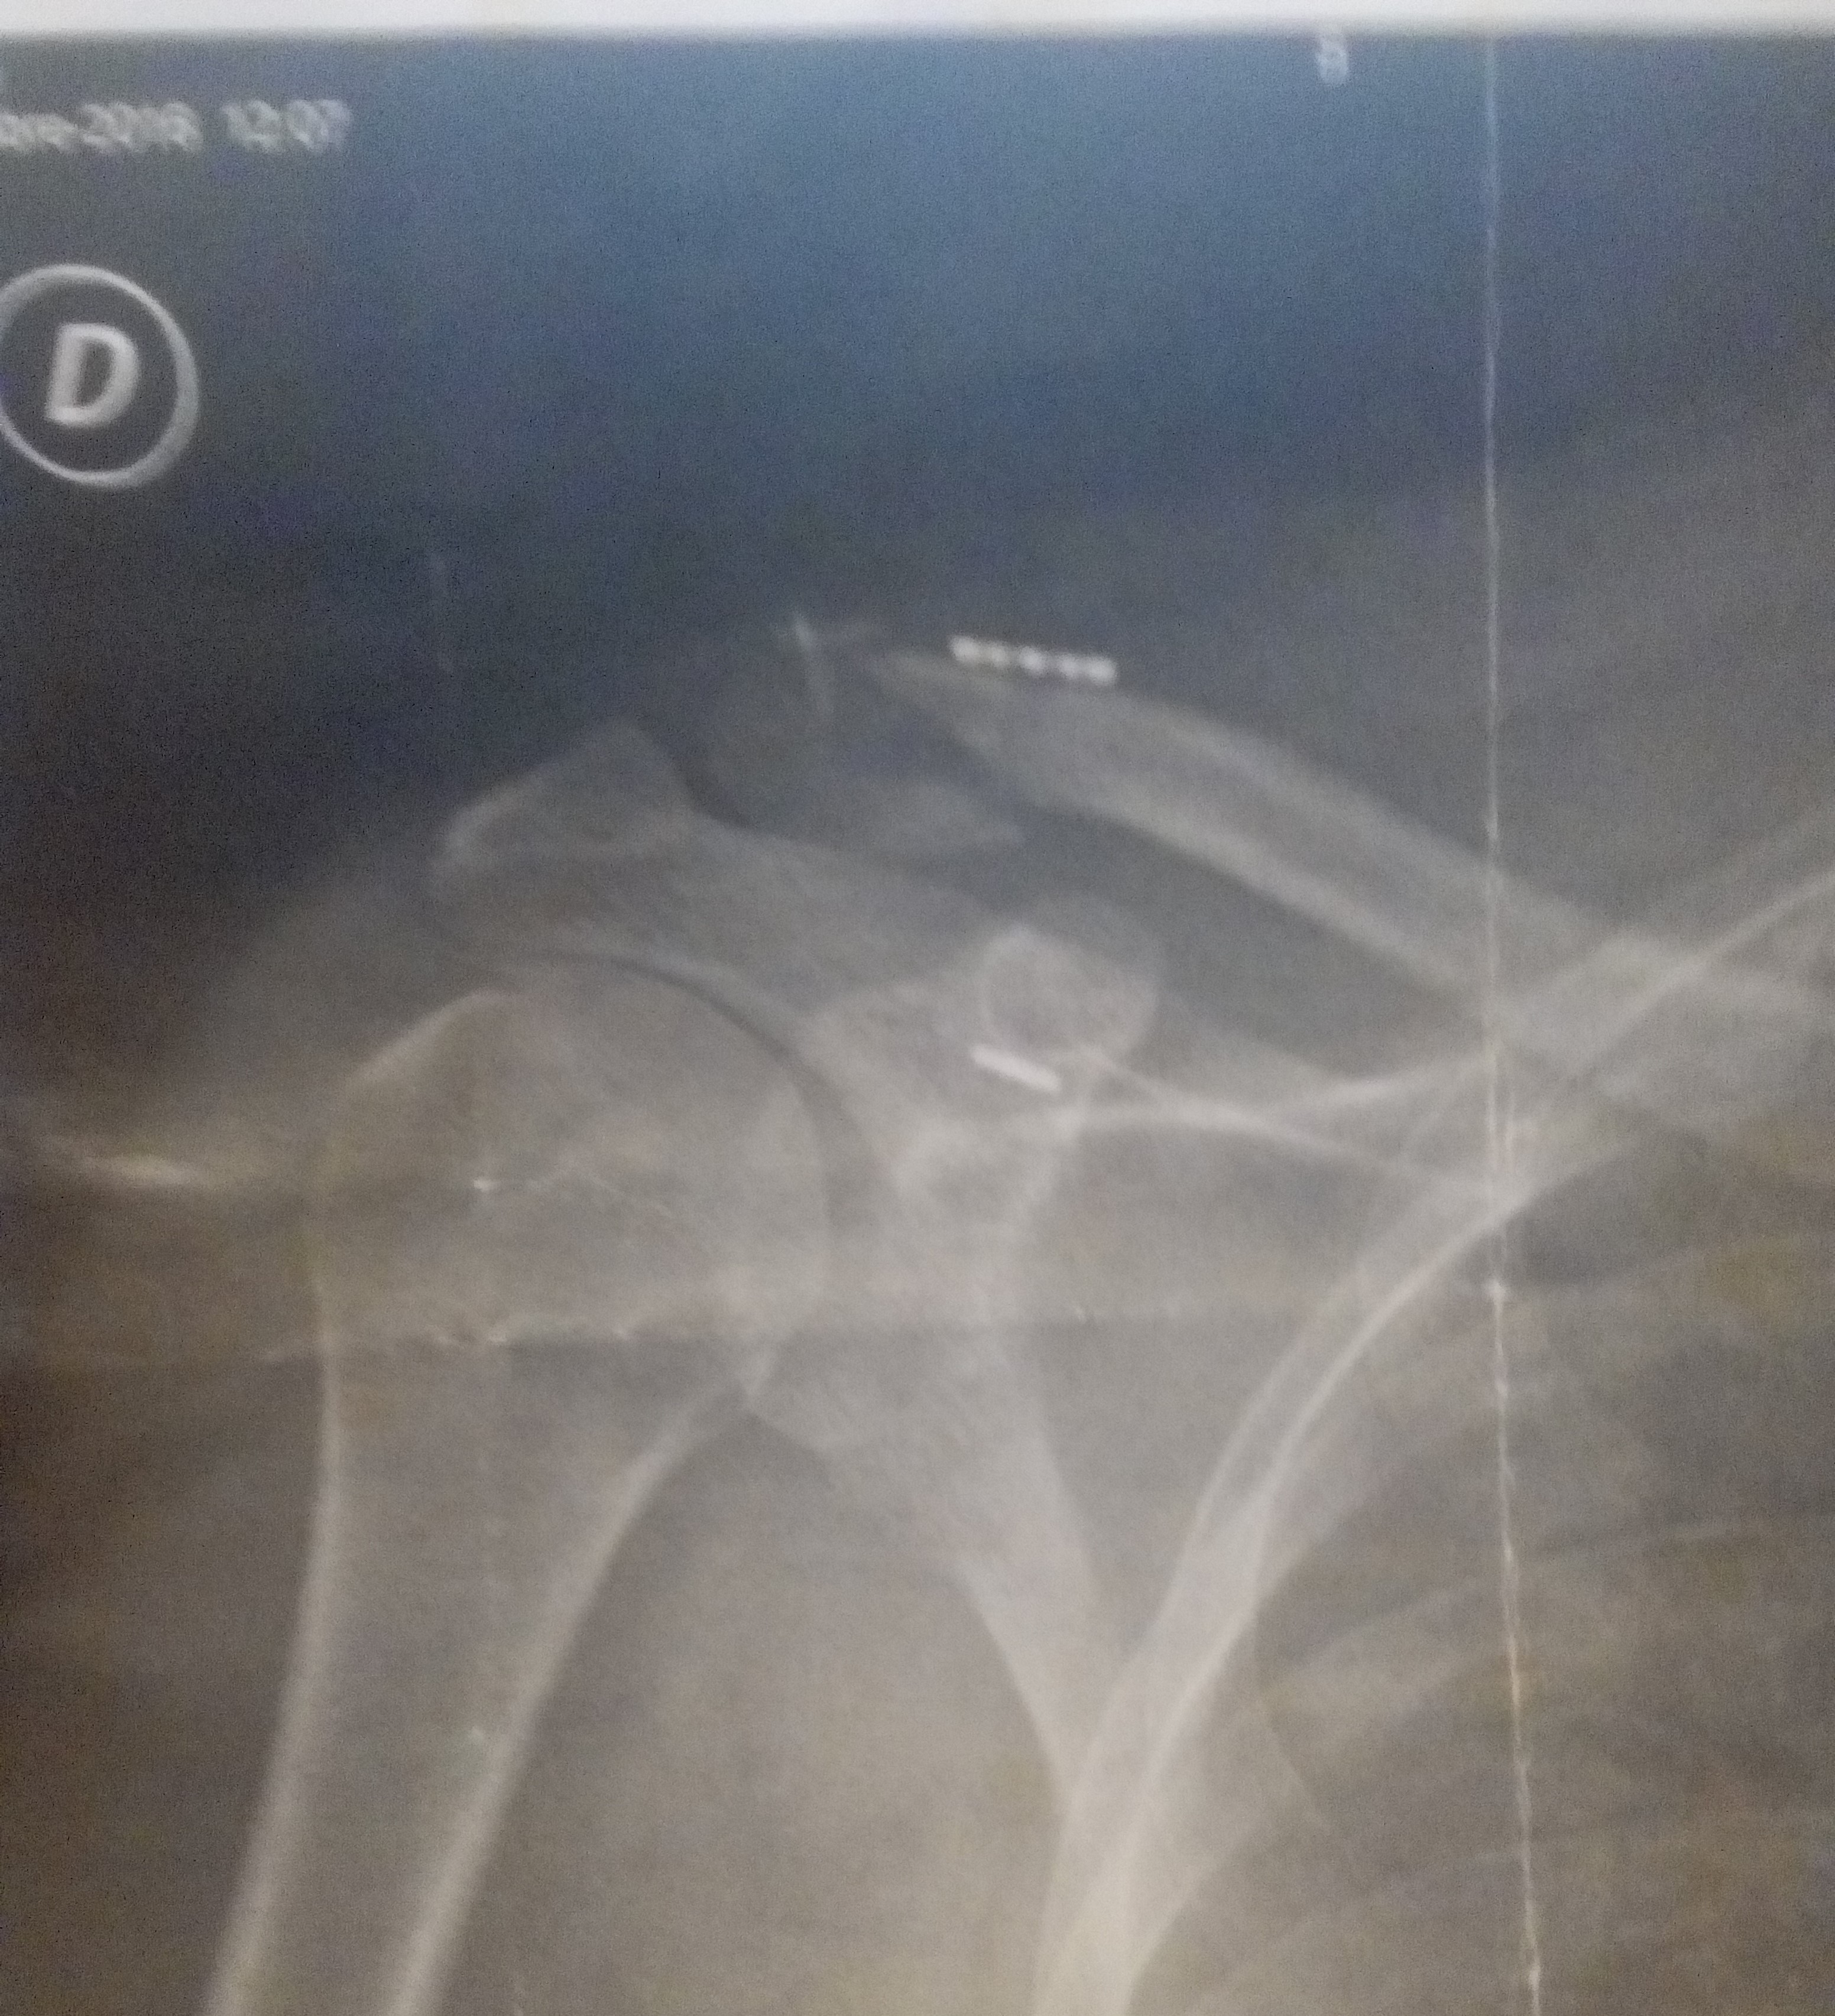

Bilan clavicule droite et pouce gauche fracturé...

Il va bien, il devrait être opéré aujourd'hui...